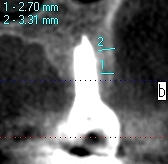

インプラントの長さ、埋入位置、方向どれも解剖学的制約を受けます。 CTによる審査診断。術後のCT審査が必要になります。| |広島市安佐南区の歯科医院 インプラントの長さ、埋入位置、方向どれも解剖学的制約を受けます。 CTによる審査診断。術後のCT審査が必要になります。 トップ お知らせ・ブログ インプラントの長さ、埋入位置、方向どれも解剖学的制約を受けます。 CTによる審査診断。術後のCT審査が必要になります。 インプラントの長さ、埋入位置、方向どれも解剖学的制約を受けます。 CTによる審査診断。術後のCT審査が必要になります。 Web診療予約 初めての方へ 選ばれ続ける理由 院内設備について 歯が痛いしみる一般歯科 歯がぐらぐらする歯周病 健康な歯を保ちたい予防歯科 子供の虫歯予防をしたい小児歯科 銀歯をセラミックに審美歯科 白い歯を目指しませんか?ホワイトニング 矯正専門医がいるので安心矯正歯科 抜けた歯を補いたいインプラント・入れ歯 医院案内 スタッフ紹介 メリィハウス歯科クリニックオフィシャルホームページ ラベンダー歯科クリニックオフィシャルホームページ お知らせ・ブログ ホーム 診療科目 一般歯科 歯周病治療 予防治療 小児歯科 審美治療 ホワイトニング 矯正歯科 入れ歯・インプラント マウスピース矯正 初めての方へ 院長・スタッフ 設備紹介 医院案内・アクセス メニューを閉じる